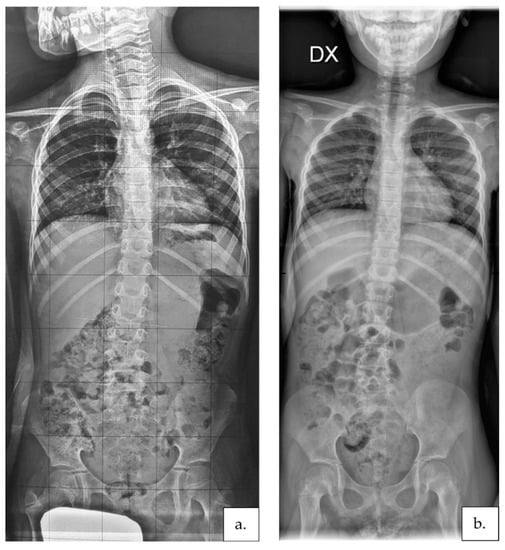

2.3.4. Scoliosis Severity